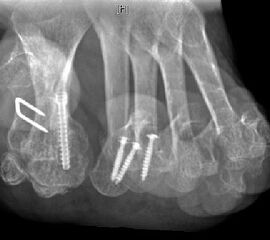

Gute Ergebnisse werden in diesem Fall durch die Arthrodese des MTP-1-Gelenkes erzielt. Bei älteren Patienten kann zum Erhalt der Beweglichkeit eine Keller-Brandes-Prozedur sinnvoll 2327, (Wirth, 2002)

Arthrodese MTP I und weichteilige Rezentrierung MTP II und III (eigenes Bildmaterial)

Abbildung 18